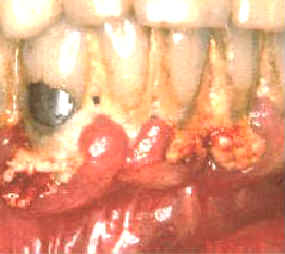

Este paciente es un varón 60 años de edad que

desea realizar tratamiento por implantes en el maxilar superior. Él

tiene un estándar socio-económico muy bueno, pero a pesar de esto,

demuestra un nivel de higiene dental muy deficiente. Las grandes

acumulaciones bacterianas están presentes a lo largo del margen

gingival en la mandíbula. Él ha perdido todos los dientes en el

maxilar superior y desea realizar implantes para así poder tener un prótesis

fija, que considera más confortable. |

El margen gingival de la mandíbula esta

intensamente inflamado y el tejido exhibe señales de daño

severo. En ciertas áreas del margen gingival se observan áreas de

necrosis . El margen gingival se encuentra retraído por la gran

cantidad de placa bacteriana y debido a esta acumulación de placa

dental hay bolsas poco profundas.

Las bacterias y las reacciones del huésped han causado un movimiento

apical del epitelio de unión con la cosnecuente pérdida de inserción

. En este caso particular el diagnóstico de las lesiones es fácil. |

| Estas imágenes muestran inmediatamente como queda luego

de la limpieza con instrumental ultrasónico.

La gingiva se desprende del diente y la mayoría del epitelio de la

bolsa periodontal queda expuesto. El sangrado durante el tratamiento es intenso y el paciente

suele notar algún sangrado post operatorio de la encía. Los tejidos

blandos suelen molestar. |